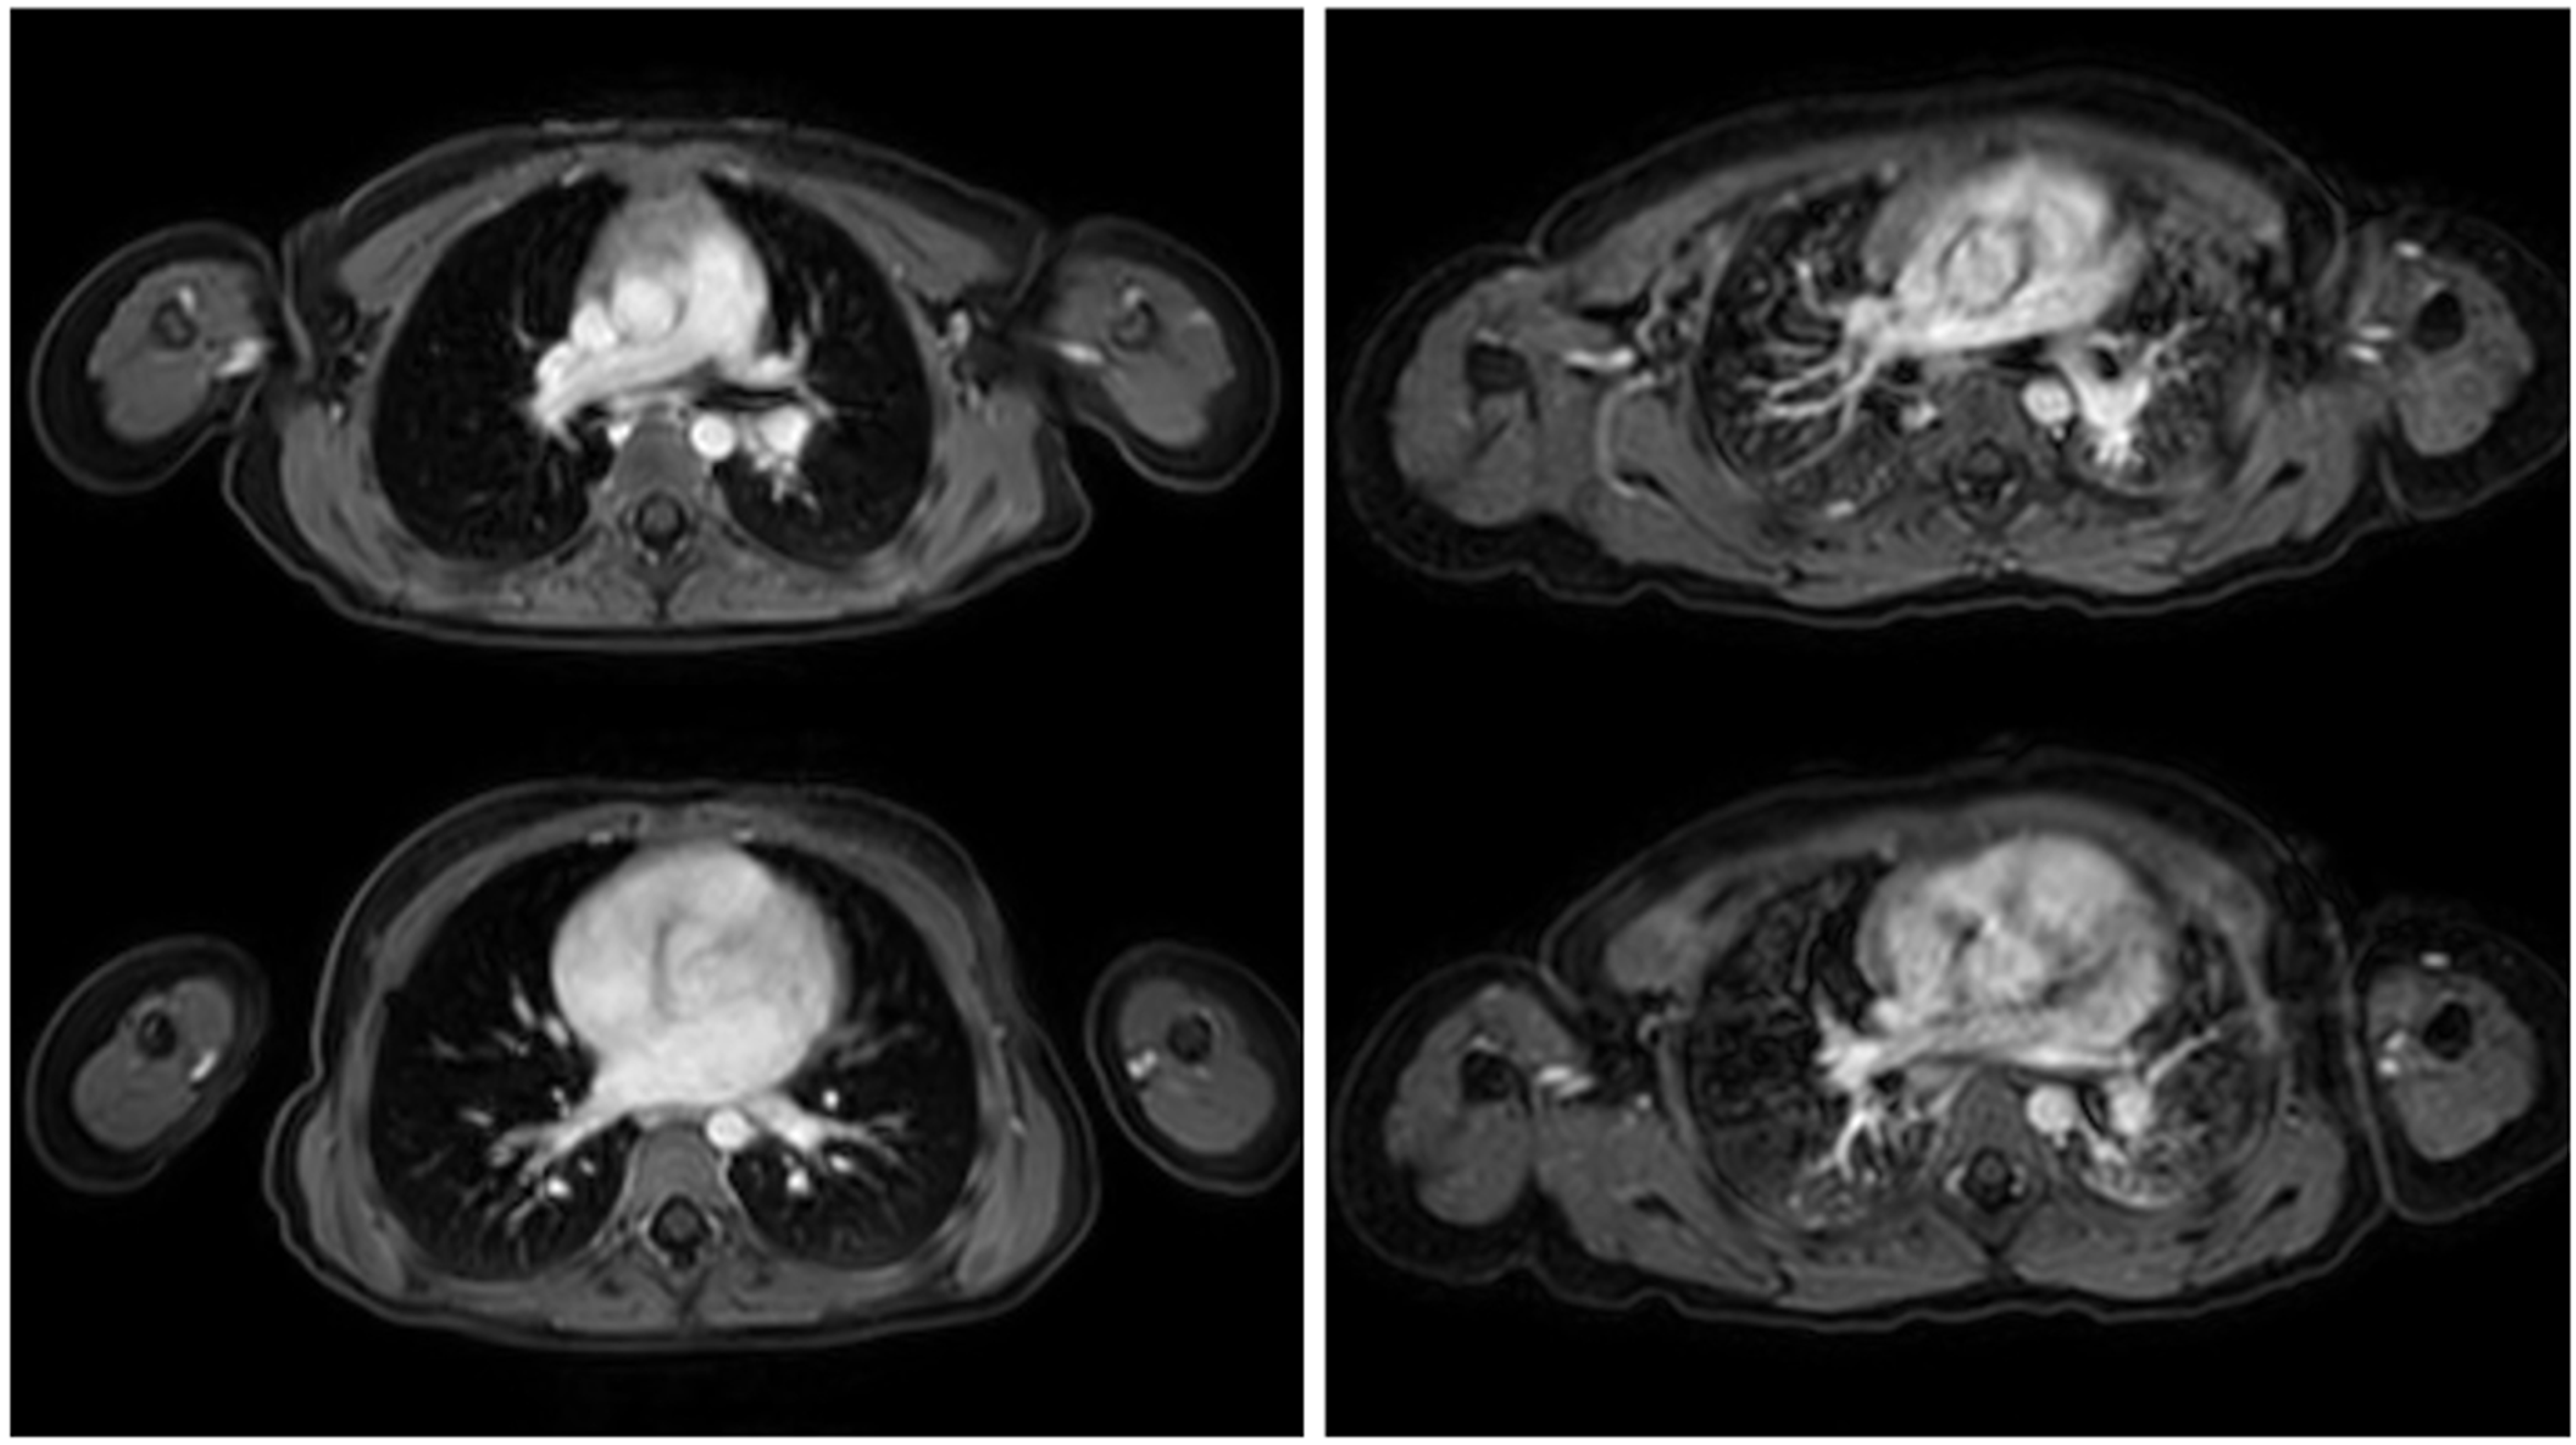

- Tischendorf, P.; Kunnemann, M.D.; Krahling, T.; Lange, J.H.; Heindel, W.; Beck, L. Thoracic MRI in Pediatric Oncology: Feasibility and Image Quality of Post-Contrast Free-Breathing Radial 3D T1 Weighted Imaging. Biomedicines 2025, 13, 2302. [Google Scholar] [CrossRef]